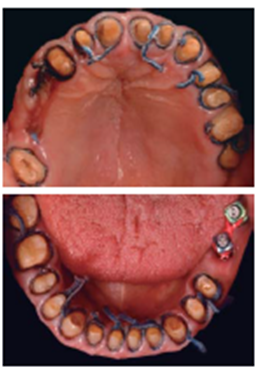

Además de indicar la especificación del incremento de DVO, en un modelo de diagnóstico se dibujó con fresa de diamante de bola, la arquitectura gingival del contorno del margen que se deseaba establecer para la confección de un encerado (Figuras 10a11).

A partir de éste se elaboraron matrices de silicona y mediante resina bisacrílica Protemp™ 4, 3M ESPE se conformó un prototipo biofuncional para verificar fonación, deglución, exposición dental, reubicación del plano incisal, línea de la sonrisa, largo y ancho de los dientes (Figura 12).

Mediante evaluación radiográfica de la relación corona-raíz, se realizó el alargamiento de la corona en el sextante anterosuperior para exponer suficiente estructura dental y lograr una retención adecuada para las restauraciones finales (Figuras 16a22).

De los dientes 13 a 23 se realizaron tratamientos de conductos en el Departamento de Endodoncia de esta institución, para permitir la colocación de material de reconstrucción intraconducto, desobturando 4 mm a partir del remanente dental más incisal y así conformar una preparación dental estable geométricamente, que ofreciera efecto férula y retención a la futura restauración (Figura 23).

Un nuevo plano oclusal se estableció preparando el arco superior e inferior para coronas completas (Figura 24).

Se adaptaron restauraciones de polimetilmetacrilato termocurable, para el segmento anterosuperior se solicitó al laboratorio dental la colocación de dientes de tablilla para conseguir un efecto más agradable visualmente. La cementación de las mismas se realizó con cemento a base de óxido de zinc y eugenol reforzado con polímeros IRM®, Densply, a cuya mezcla se le añadió Maxitrol® por sus propiedades antibióticas, así como antiinfl amatorias (Figuras 25a28).